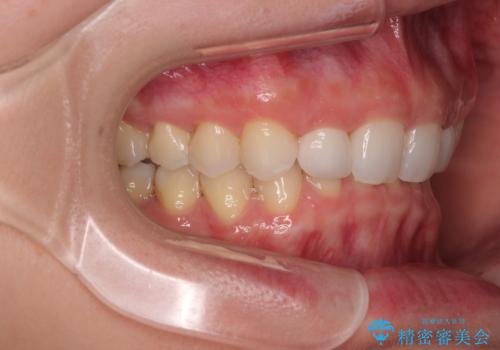

前歯のデコボコと小さい歯を改善 インビザラインとオールセラミッククラウン

- 前歯のデコボコと左右の矮小歯を気にして来院された患者様です。

矮小歯の前後にスペースを作るようにインビザライン矯正治療を計画し、矯正治療後にオールセラミッククラウンによる補綴治療を行うこととしました。

アンカースクリューを用いて上顎歯列全体を後方移動させ、極力過蓋咬合も改善されるよう計画しました。

インビザラインは長時間装着を自己管理する必要がありますが、残念ながら十分な時間の装着を行うことができませんでした。

何とか矮小歯を改善するスペースを作ることはできましたが、過蓋咬合を改善するには至りませんでした。